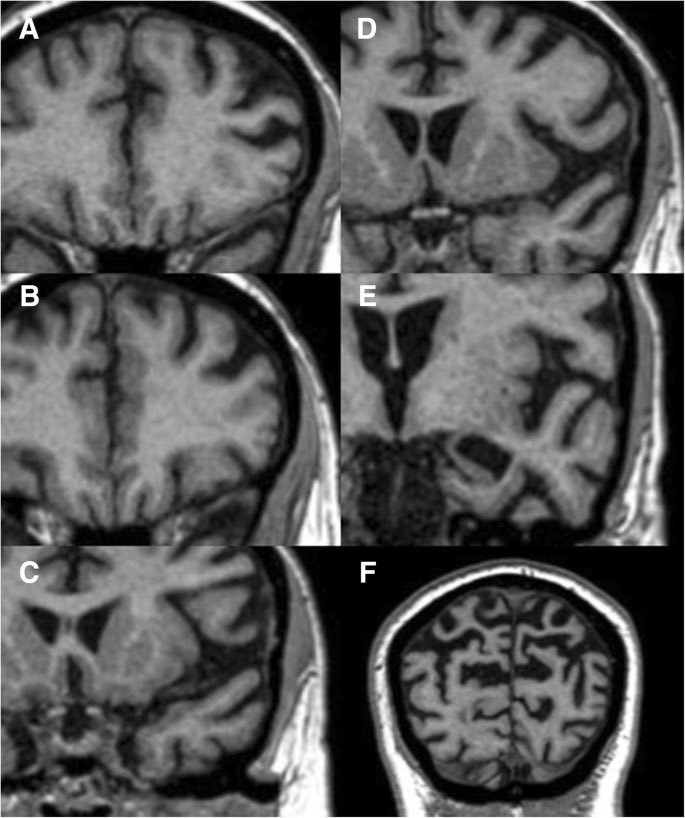

4️⃣ صِغَر حجم بعض أجزاء الدماغ، على سبيل المثال

smaller hippocampal volume